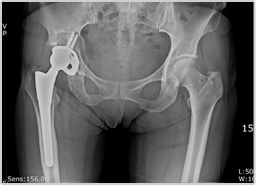

재치환술

성공적인 인공 관절 수술 후 사라졌던 고관절 동통이 수술 후 몇 년이 지나서 다시 나타나고, 점차 심해져 보행이 어려워질 때는 주치의사에게 진찰을 받은 후 인공고관절 재수술을 고려할 수 있다.

수술 전 수술 후

수술전 사진 수술후 사진